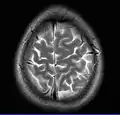

This axial T2-weighted (CSF white) MR scan shows a normal brain at the level of the lateral ventricles.